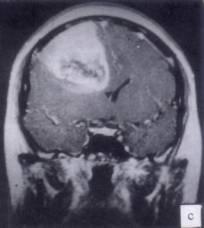

问题 病历摘要:??患者男性,52岁。头痛伴呕吐2月,呕吐呈喷射性。既往身体健康。体检:神清,表情淡漠,反应迟钝,双眼底视神经乳头明显水肿,左鼻唇沟稍浅,左腹壁反射减弱,左上下肢肌力4级,左Babinski征(-)。 下列关于多形性胶质母细胞瘤的叙述哪些是正确的?提示:肿瘤病理报告为多形性胶质母细胞瘤